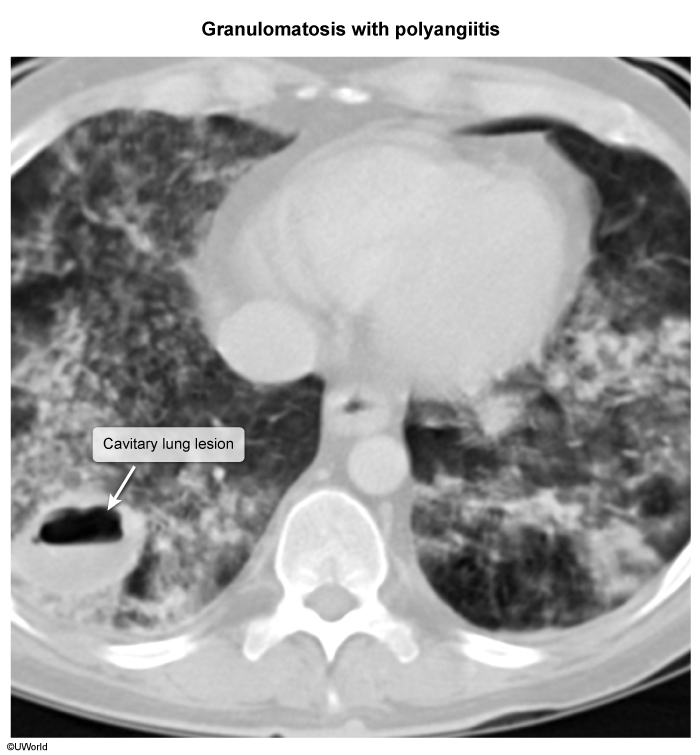

Activated neutrophils cause endothelial damage via respiratory oxidative burst (eg, MPO) and protease activity (eg, PR3). The neutrophils lodge within small vessels such as glomerular tufts and pulmonary capillaries, explaining the prominent involvement of the kidneys and lungs.  Histology of GPA reveals fibrinoid necrosis (amorphous debris representing lysis of the media

image 1

, dense neutrophilic inflammation of the vessel wall (

image 2

, and perivascular necrotizing granulomas.  The granulomas likely represent a T cell–mediated type IV hypersensitivity response to exposed self-antigens.  Histology of EGPA and MPA are similar to that of GPA but with some key differences, which are discussed later.

• Pulmonary parenchymal involvement includes nodular opacities, consolidations, and cavitary pulmonary infiltrates representing areas of lung inflammation and necrosis (

image 3